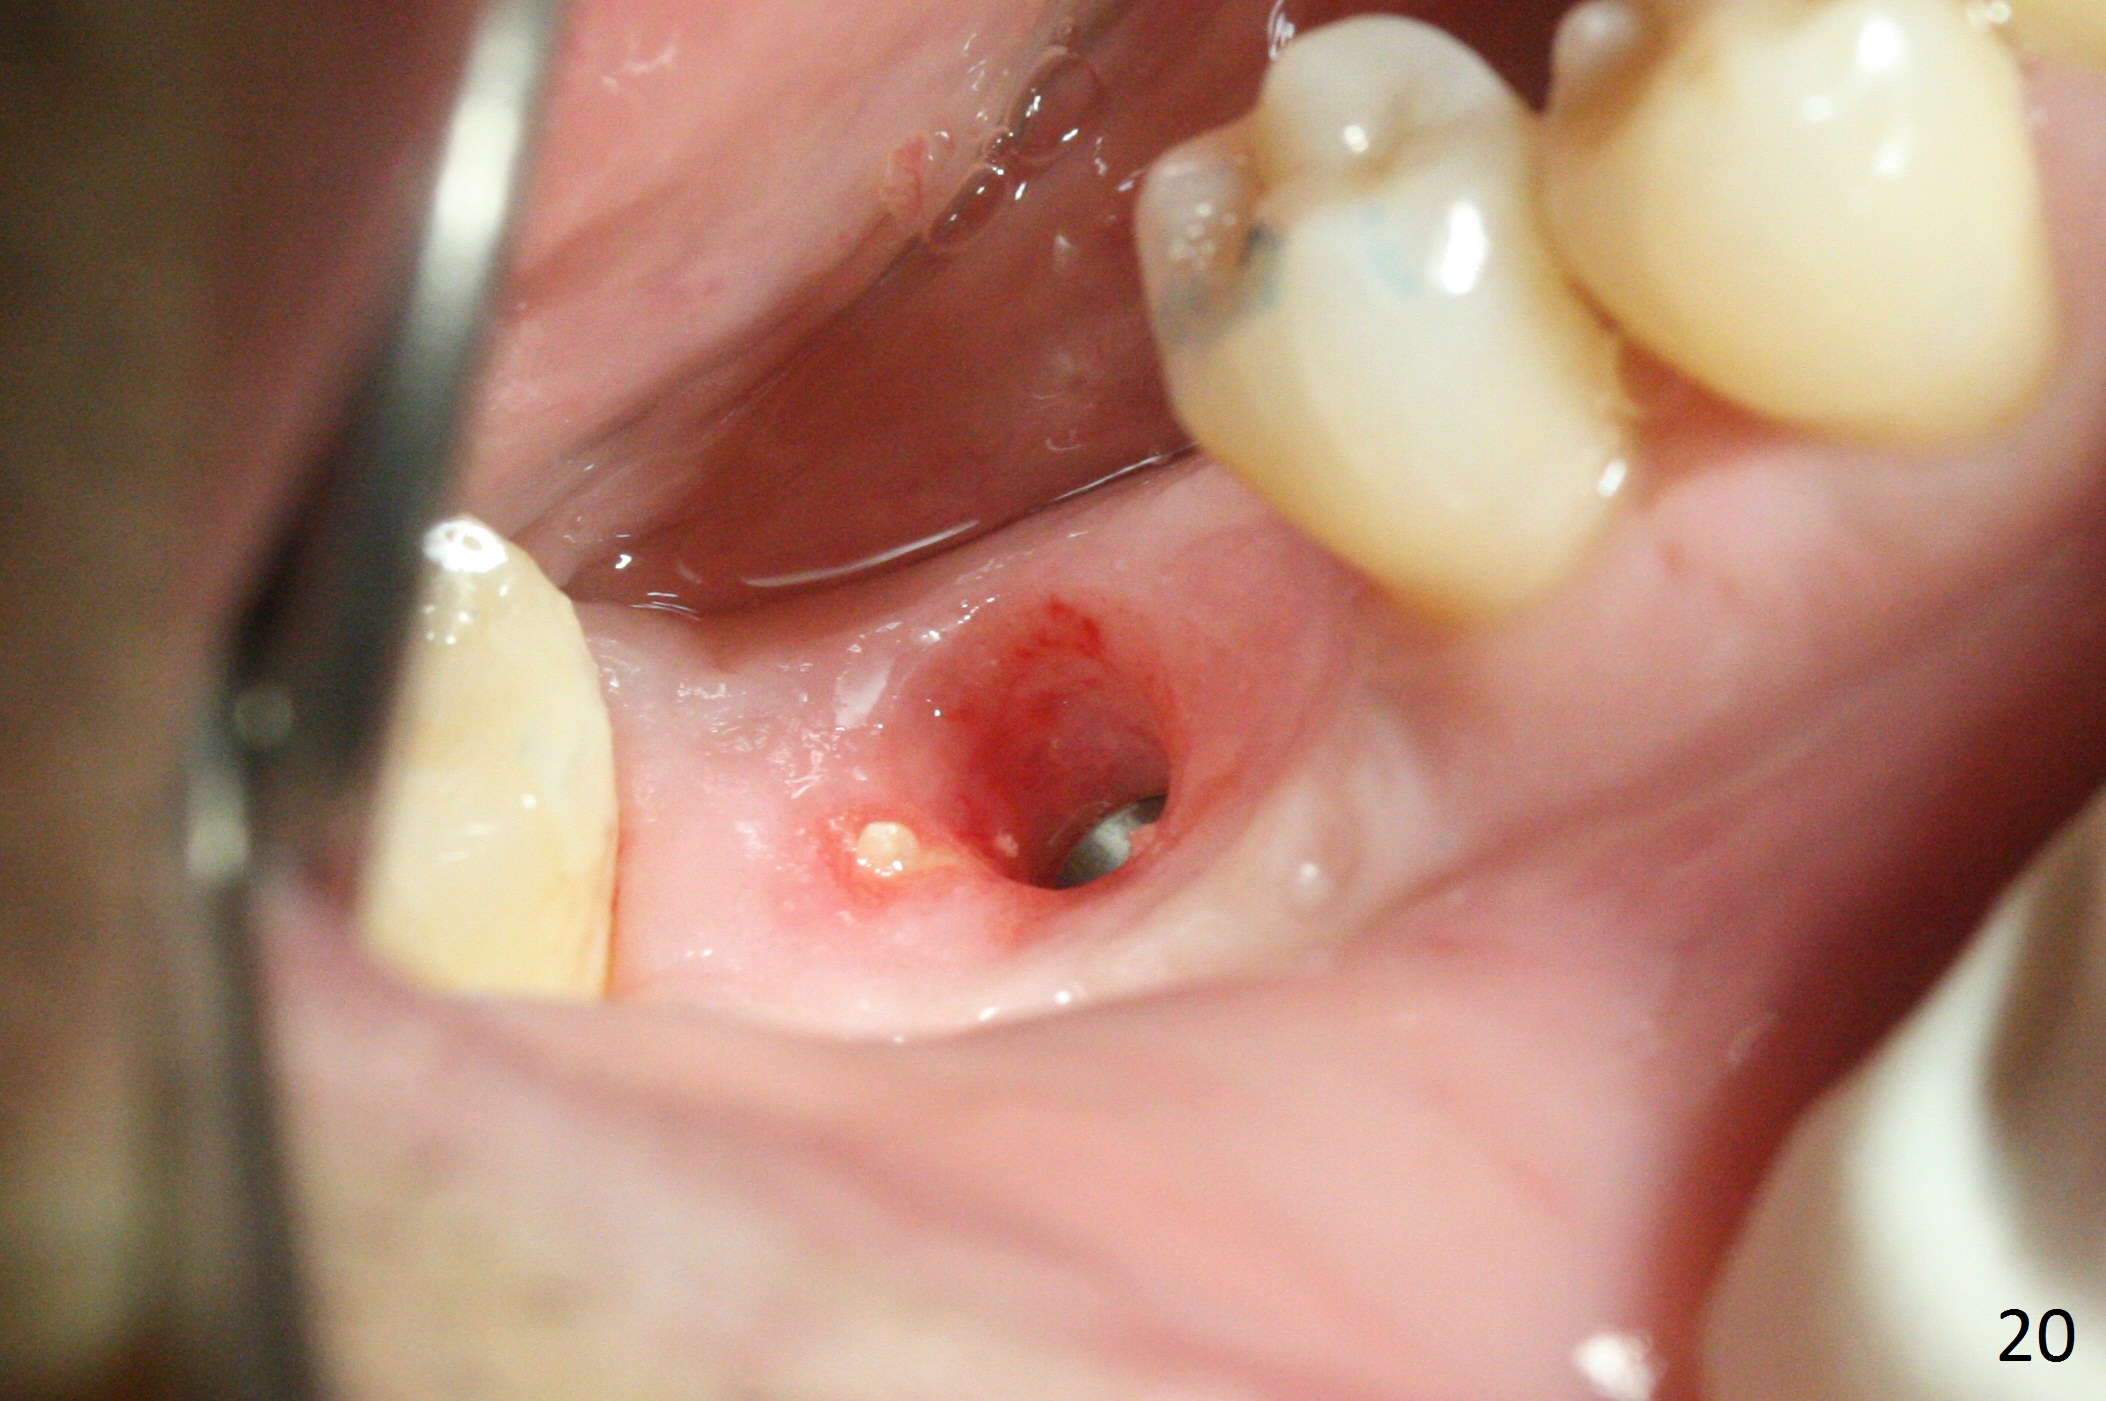

Three weeks later (5.5 months postop), a permanent crown tries in with healthy keratinized gingiva (Fig.18). The provisional keeps normal gingival bed (Fig.19), while the abutment forms tissue cuff (Fig.20). After cementation, PA shows bone regeneration (Fig.21). The gingiva remains healthy 8.5 months post cementation (Fig.22). Bone density around the implant increases 1 year 2 months post cementation (Fig.24). The gingiva remains healthy 2 years 4 months post cementation (Fig.25).